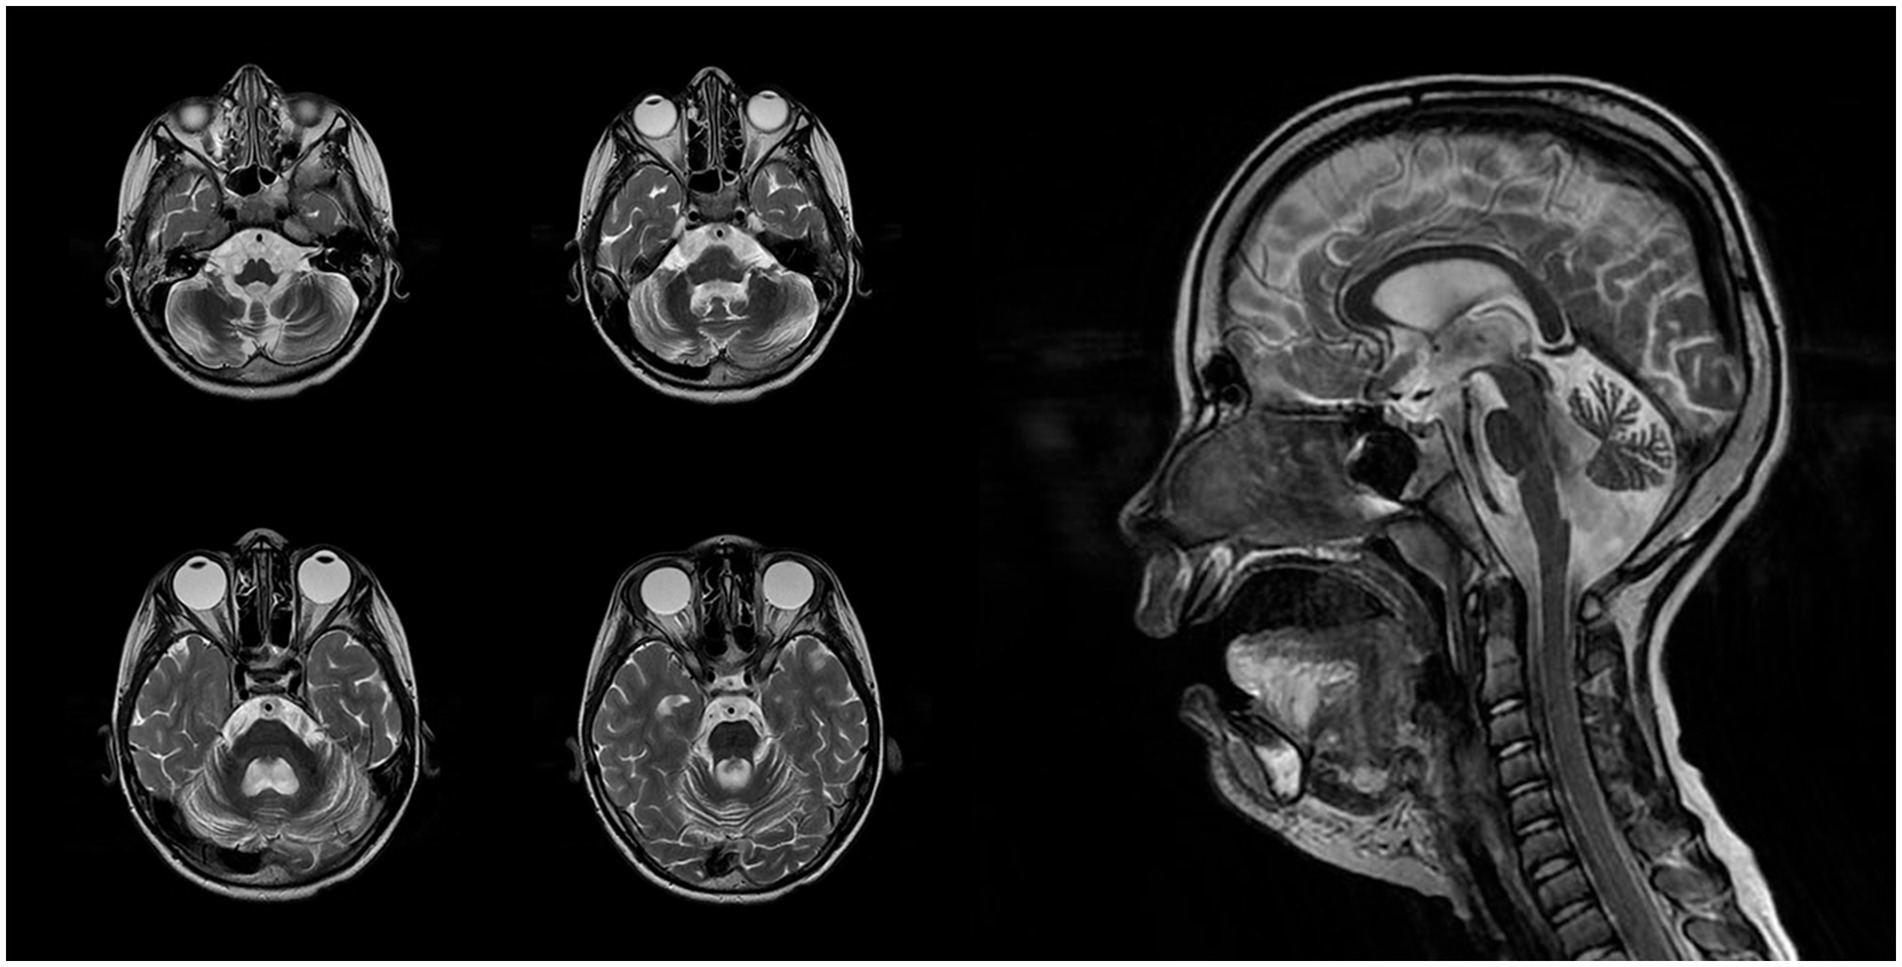

At 7 years and 6 months, a follow-up brain MRI with intravenous contrast revealed progression of cerebellar atrophy, cerebral subatrophy, and lateral ventricular dilatation measuring up to 14 mm (Figure 2). Mild leukoencephalopathy persisted in the periventricular parietal white matter. No displacement of midline structures was observed, and the subarachnoid spaces remained within normal limits. The hippocampal, parahippocampal, and hypothalamic–pituitary regions appeared structurally intact, and the craniovertebral junction was normally formed. No pathological contrast enhancement was observed. Overall, sequential imaging demonstrated stable disease without significant progression over time.

Figure 2

Magnetic resonance imaging of the patient’s brain performed in 7 years 6 months ago.

The first MRI was performed at the age of 5 years (Figure 1). An axial T2-weighted image demonstrated pronounced widening of the cerebellar sulci and enlargement of the cisternal spaces in the posterior cranial fossa, indicative of moderate cerebellar volume loss consistent with cerebellar atrophy (Figure 1A). An axial T2-FLAIR image revealed mild periventricular leukoencephalopathy involving the white matter of the frontal and parietal lobes (Figure 1B). A sagittal T1-weighted image showed reduced cerebellar volume and expansion of the posterior cranial fossa, clearly illustrating cerebellar atrophy (Figure 1C). A follow-up MRI was conducted at the age of 7 years and 6 months due to progression of neurological symptoms (Figure 2). From a dynamic perspective over the observed interval, no significant changes were noted compared to the previous imaging. An EEG performed at 7 years and 6 months during wakefulness (Figure 3A) revealed cortical rhythms inconsistent with the patient’s age, characterized by generalized disorganization and epileptiform discharges. Daytime EEG recordings during both wakefulness and sleep (Figure 3B) confirmed markedly disorganized cortical activity with prominent epileptiform features. WES identified a homozygous variant: chr13:76995929AG > A, CLN5(NM_006493.4):c.368del (p.Arg123LysfsTer4), which was classified as pathogenic according to ACMG criteria (PVS1, PM2, PM3). Sanger sequencing confirmed the variant and the patient’s homozygous status.